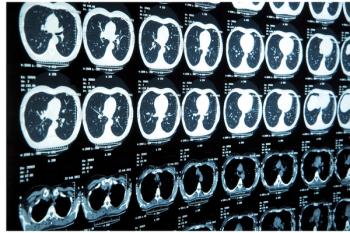

Case History: 74-year-old male smoking 48 packs/year with history of severe dyspnea.